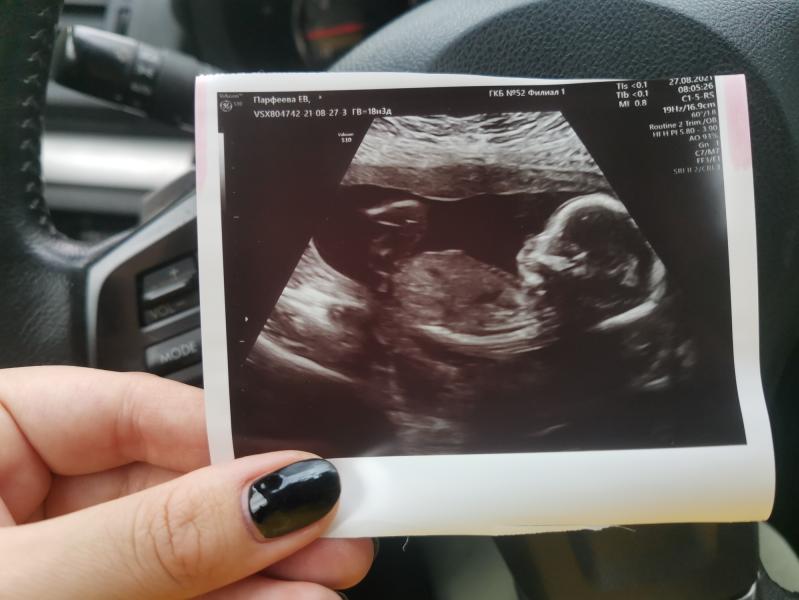

2й скрининг)).

Пришла сегодня 18.5 по месячным и 18.3 по первому скринингу). Я спрашивала у врача в жк не рано ли она меня записала, она сказала в самый раз. 🙈

Так вот мы с сыном подготовились, приехали на 30 минут раньше гуляли кругами вокруг больницы, съели пирожок из макдака и гляссе выпили)) на 1м скрининге просто 3 часа будила ребенка и с 4го раза только смогли все посмотреть, поэтому тут подготовились).